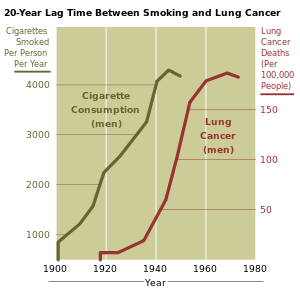

Smoking

Smoking, particularly of cigarettes, is by far the main contributor to lung cancer. Across the developed world, almost 90% of lung cancer deaths are caused by smoking. In the United States, smoking is estimated to account for 87% of lung cancer cases (90% in men and 85% in women). Among male smokers, the lifetime risk of developing lung cancer is 17.2%. Among female smokers, the risk is 11.6%. This risk is significantly lower in non-smokers: 1.3% in men and 1.4% in women. Cigarette smoke contains over 60 known carcinogens including radioisotopes from the radon decay sequence, nitrosamine, and benzopyrene. Additionally, nicotine appears to depress the immune response to malignant growths in exposed tissue.

The length of time a person smokes as well as the amount smoked increases the person's chance of developing lung cancer. If a person stops smoking, this chance steadily decreases as damage to the lungs is repaired and contaminant particles are gradually removed. In addition, there is evidence that lung cancer in never-smokers has a better prognosis than in smokers, and that patients who smoke at the time of diagnosis have shorter survival than those who have quit.

Lung cancer was extremely rare before the advent of cigarette smoking; it was not even recognized as a distinct disease until 1761. Different aspects of lung cancer were described further in 1810. Malignant lung tumors made up only 1% of all cancers seen at autopsy in 1878, but had risen to 10–15% by the early 1900s. Case reports in the medical literature numbered only 374 worldwide in 1912, but a review of autopsies showed that the incidence of lung cancer had increased from 0.3% in 1852 to 5.66% in 1952. In Germany, in 1929 physician Fritz Lickint recognized the link between smoking and lung cancer, which led to an aggressive anti-smoking campaign. The British Doctors Study, published in the 1950s, was the first solid epidemiological evidence of the link between lung cancer and smoking. As a result, in 1964 the Surgeon General of the United States recommended that smokers should stop smoking.